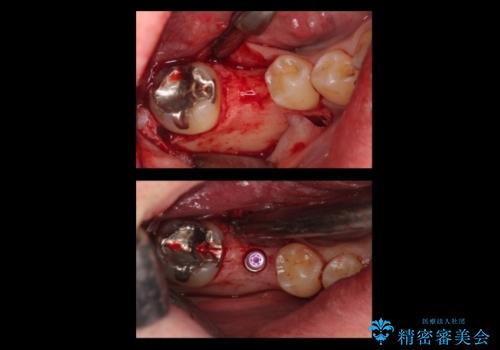

- 右下の奥歯にインプラントを入れたいと来院。

抜歯から時間が経っており、骨が十分あったためすぐにインプラントを入れることが可能でした。骨も補う必要がありませんでした。

手術が怖いとのことで、外科手術時には静脈麻酔を行い、眠っている間に手術が終わるようにしました。

インプラントの術式は比較的単純で、難しくないですが、予後を見据えて角化歯肉を増やす手間をかけることが大変重要です。

インプラント手術時に同時に親知らずの抜歯も行い、腫れや痛みなどを1度で終わらせるようにしました。